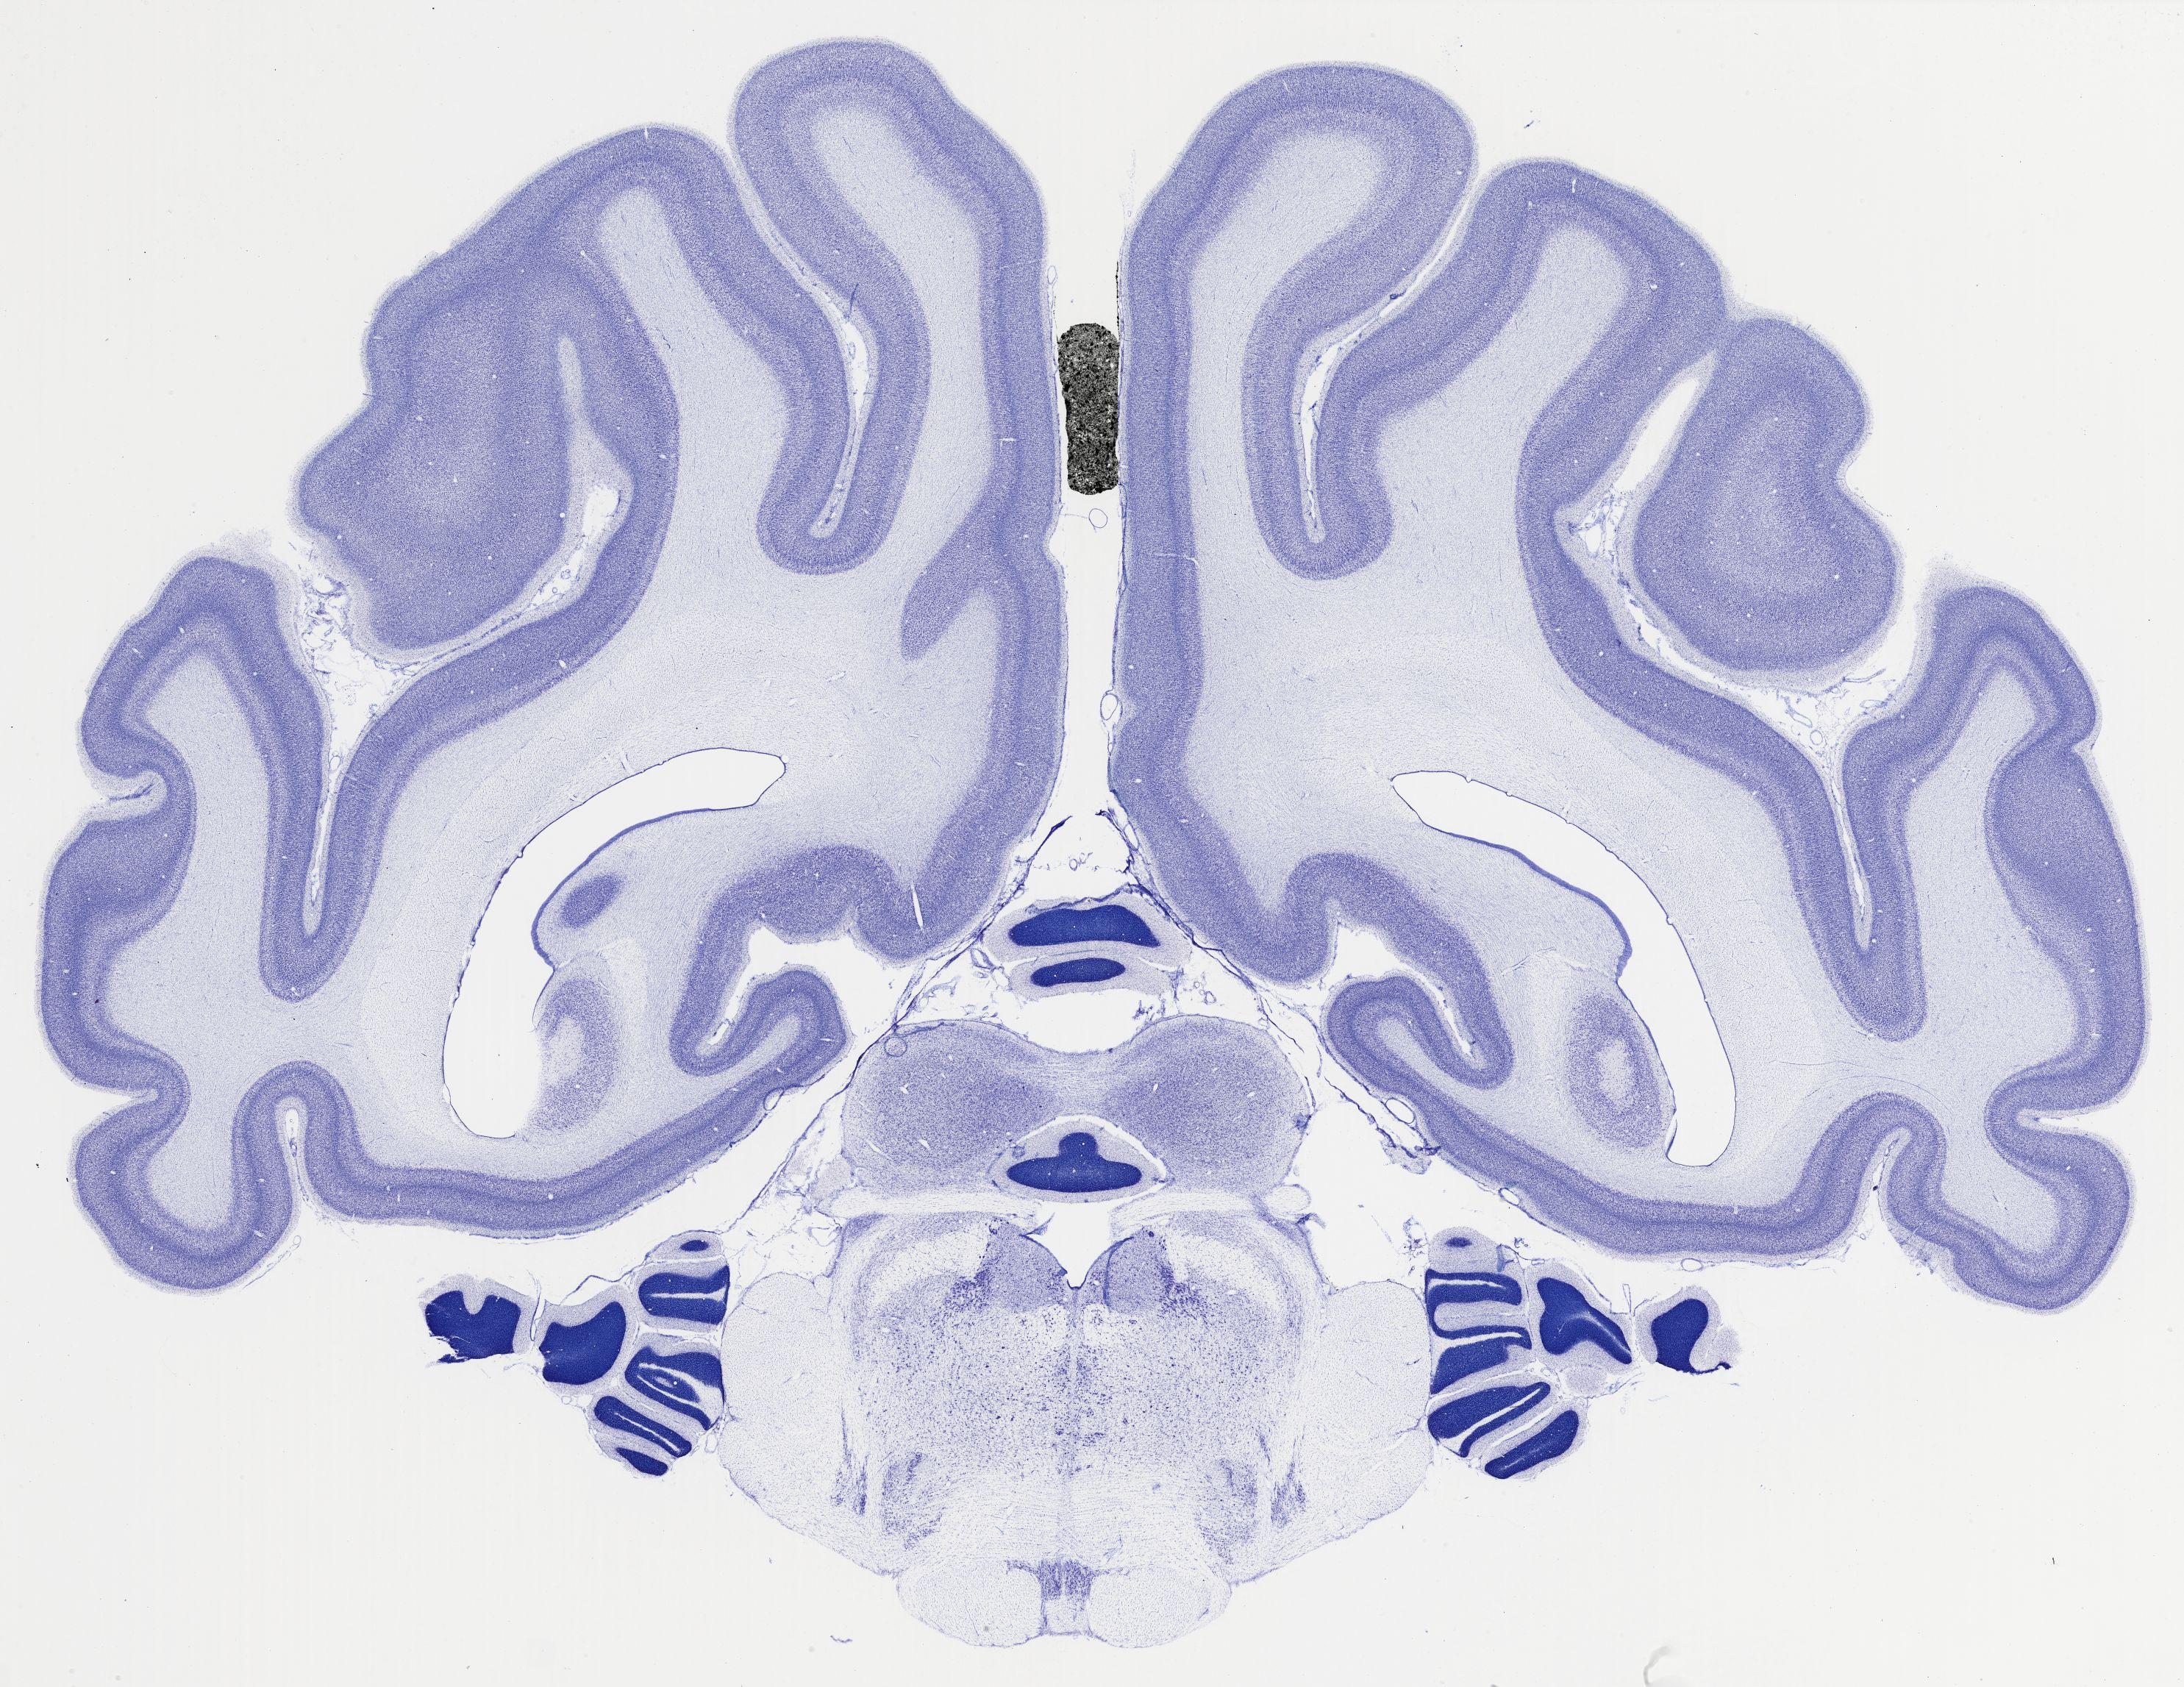

Datasets -> Chlorocebus Aethiops -> Nissl, coronal, histo, Whole-Brain, adult

[ Metadata ]   ·   Source: NeuroScience Associates

thumbnail

523